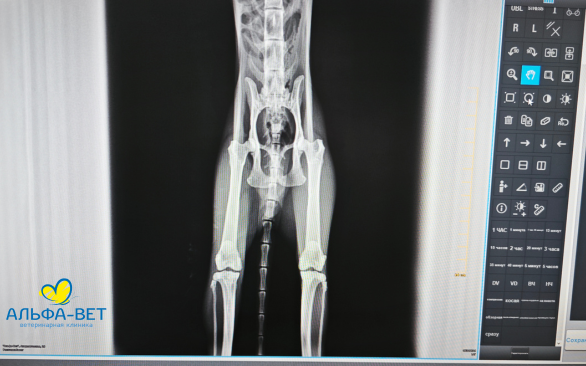

Участники получили возможность разобрать на практике алгоритм работы с рентгеновскими снимками и их описанием, рассмотрели типовые ошибки. Смогли закрепить на практике основные способы укладки питомцев, чтобы по возможности получать максимально информативные рентгеновские снимки.